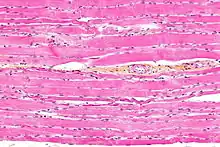

Les rhabdomyocytes sont les cellules musculaires des muscles striés squelettiques[1]. Ils se forment par fusion de myoblastes, donnant des myotubes à noyaux centraux qui, sous l'effet de l'innervation [Comment ?] vont se différencier en myofibres (à noyaux périphériques). À la suite du processus de croissance, on assiste à l'augmentation de la taille des fibres (en longueur et en épaisseur par adjonction ce cellules satellites embryonnaires) donnant ainsi les cellules musculaires striées [réf. souhaitée].

Elles ont la caractéristique de comporter un grand nombre de noyaux (en moyenne 100) situés en périphérie du cytoplasme (sous la membrane plasmique) et de former ainsi les syncytiums [réf. souhaitée]. Ce sont les unités contractiles du muscle grâce à l'organisation de leurs myofilaments d'actine et de myosine à même de « glisser » les uns par rapport aux autres, sous l'impulsion d'un influx nerveux.

Les rhabdomyocytes sont de grandes cellules, ayant un diamètre variant de 10 à 100 micromètres pour une longueur de 1 à 5 cm[2].